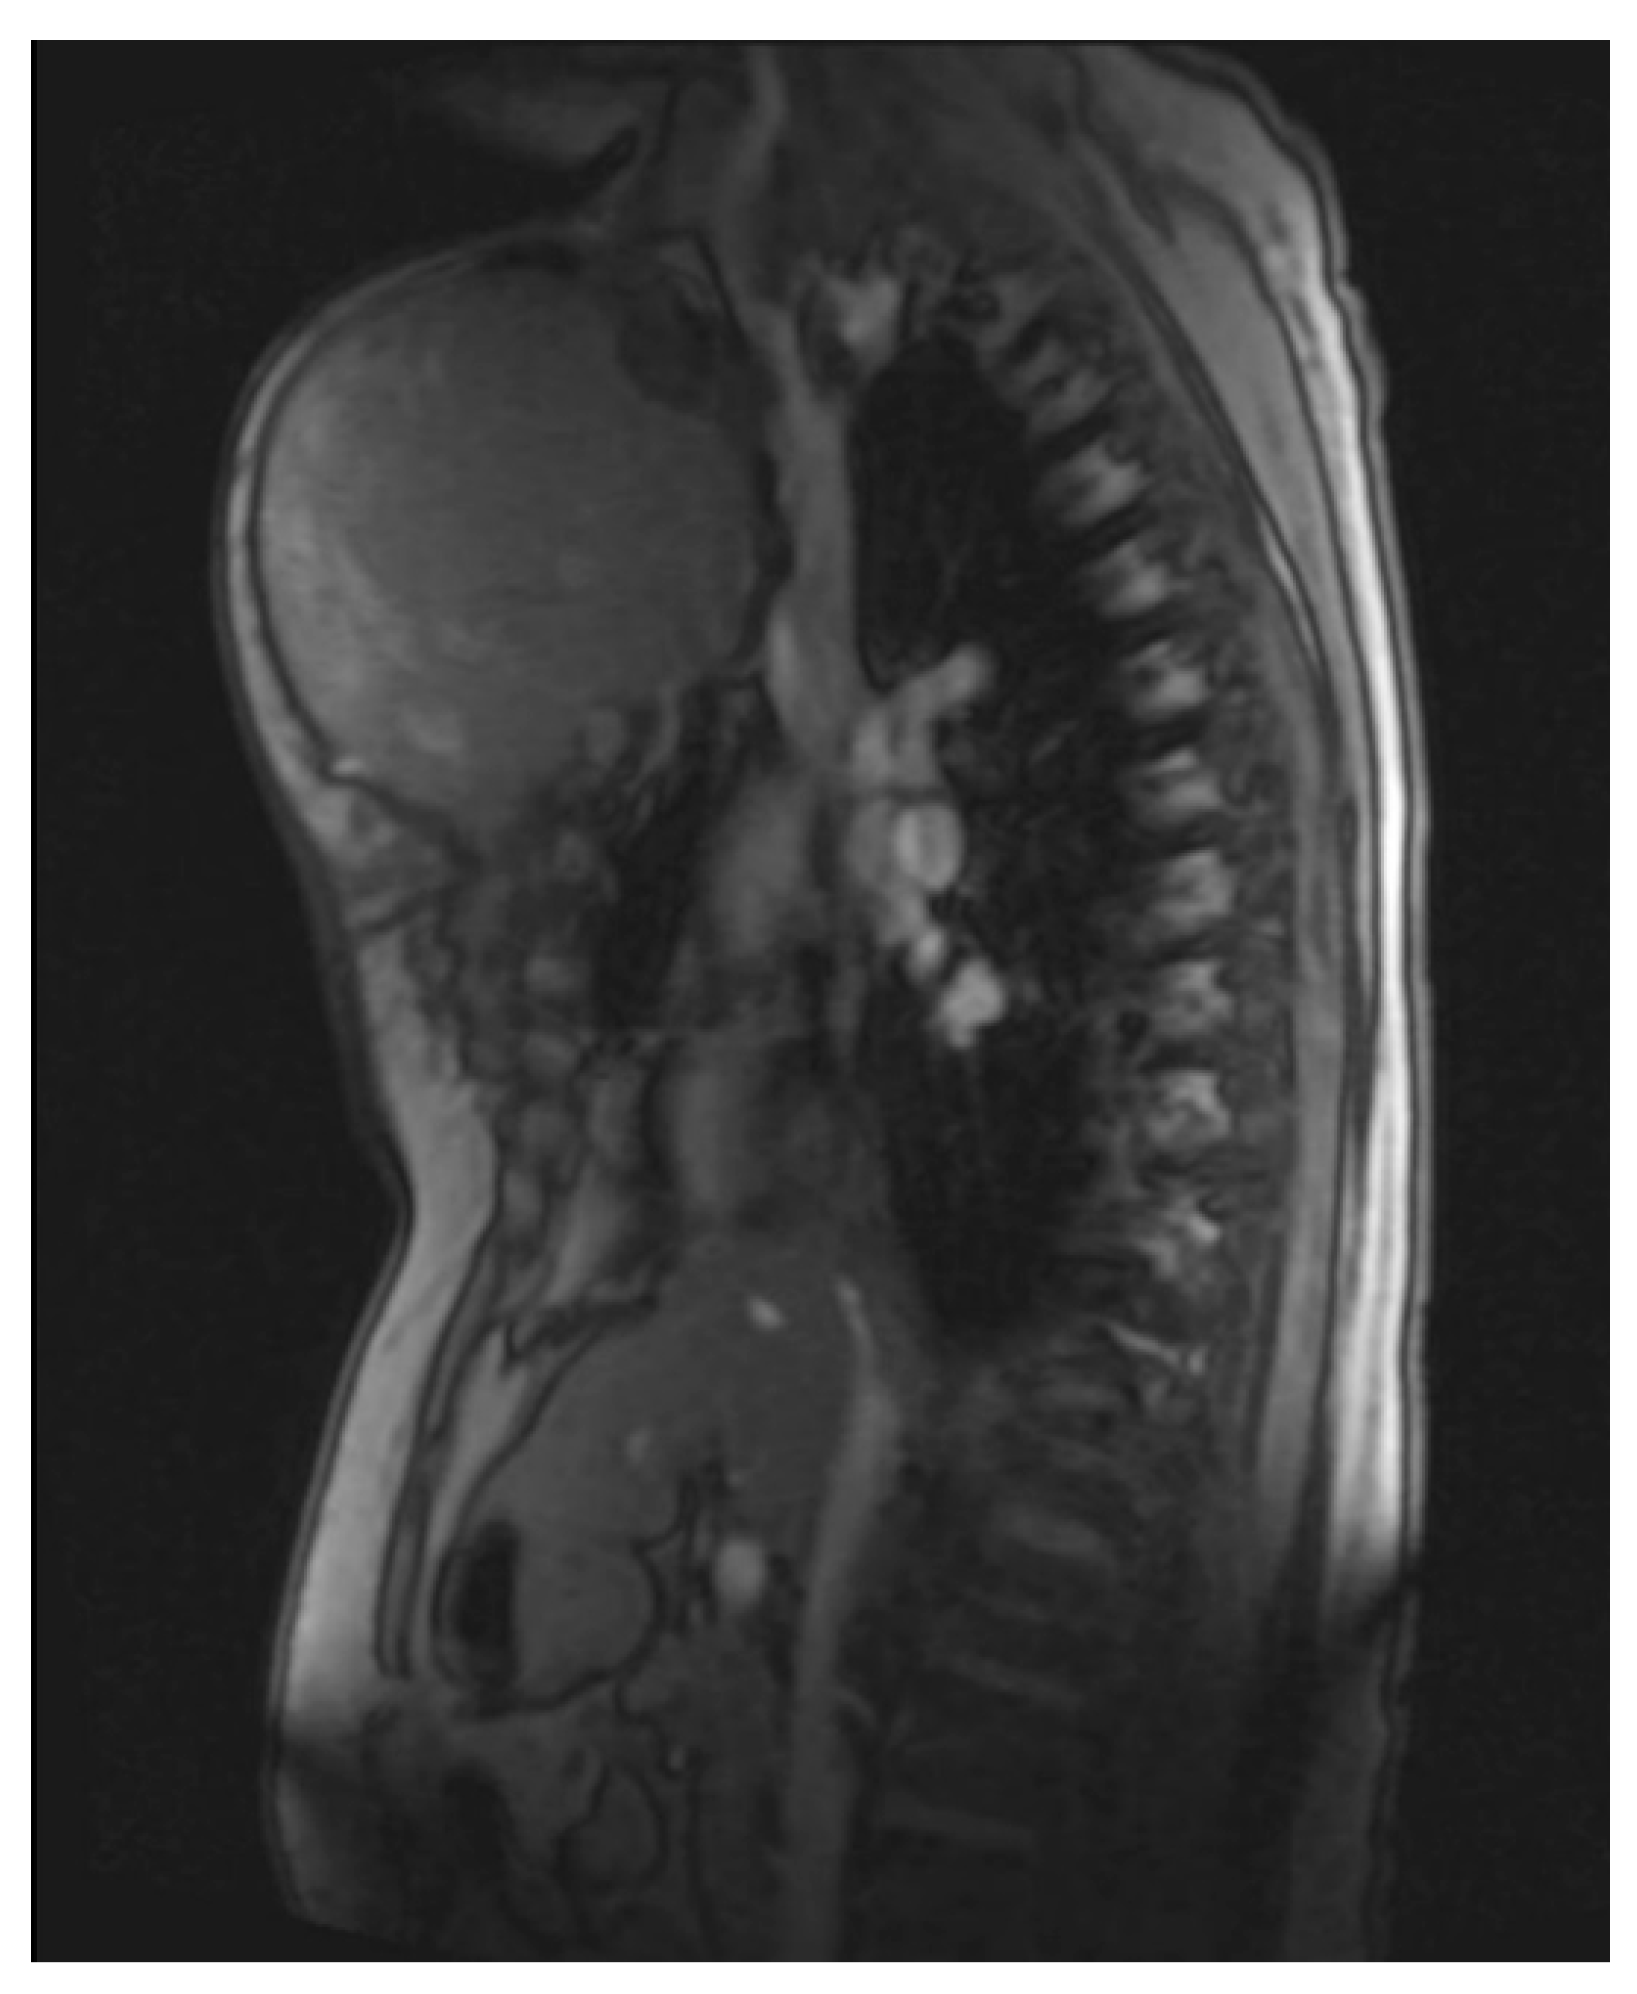

She returned to Bochum in June 2018 with the following symptoms: on the right ventral chest wall, she had a large tumor with a perforation in the pericardium of approximately 15 × 20 cm, an abdominal inguinal tumor on the right, and an ulcerating tumor on the lower left side of the abdomen. A computed tomography of the thorax and abdomen was performed in 09/2018 (Figure 2 and Figure 3) and a magnetic resonance imaging of the thorax was performed in 06/2018 (Figure 4 and Figure 5).

Figure 4.

Magnetic resonance imaging (MRI 2018) showing the large tumorous masses on the anterior thoracic wall, infiltration of the mediastinum per continuitatem, and contact with the aorta.